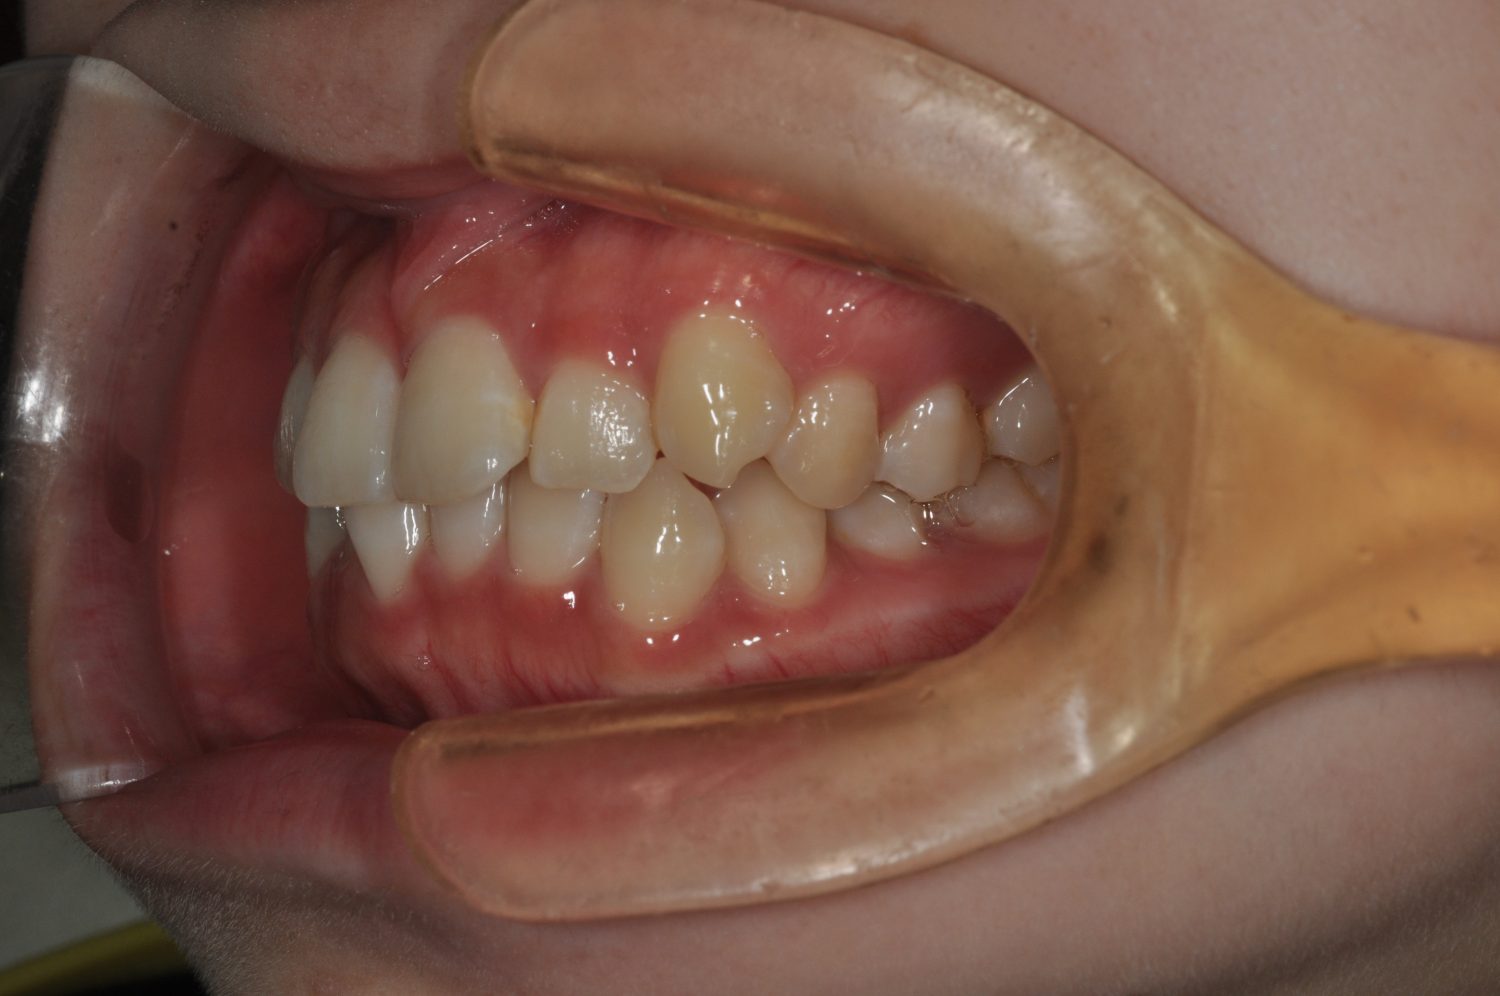

| 主訴 | 前歯部の叢生と正中の不一致 |

| 治療内容 | 軽度の叢生の改善を行うために、非抜歯でのマルチブラケット装置による治療を行った。 |

Ⅰ期治療で叢生、反対咬合の改善をセクショナルアーチとMPAを使用して改善した後、成長観察を行っていました。永久歯の萌出したため、Ⅱ期治療を開始することとなった。上下顎とも骨格的に問題がなかったため、非抜歯で治療を行った。